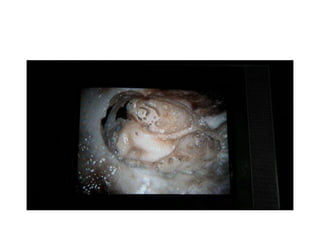

APICAL TURN / SUPERIOR TURN

cochleostomy in middle cranial

fossa approach

So the indication of middle cranial fossa superior

cochleostomy insertion is in infected cases after CWD

+ SP ( subtotal petrosectomy ) We can do redo by fat

risnced in rifampacin . But if you want to go by sterile

area middle cranial fossa superior cochleostomy &

reverse insertion & reverse programming